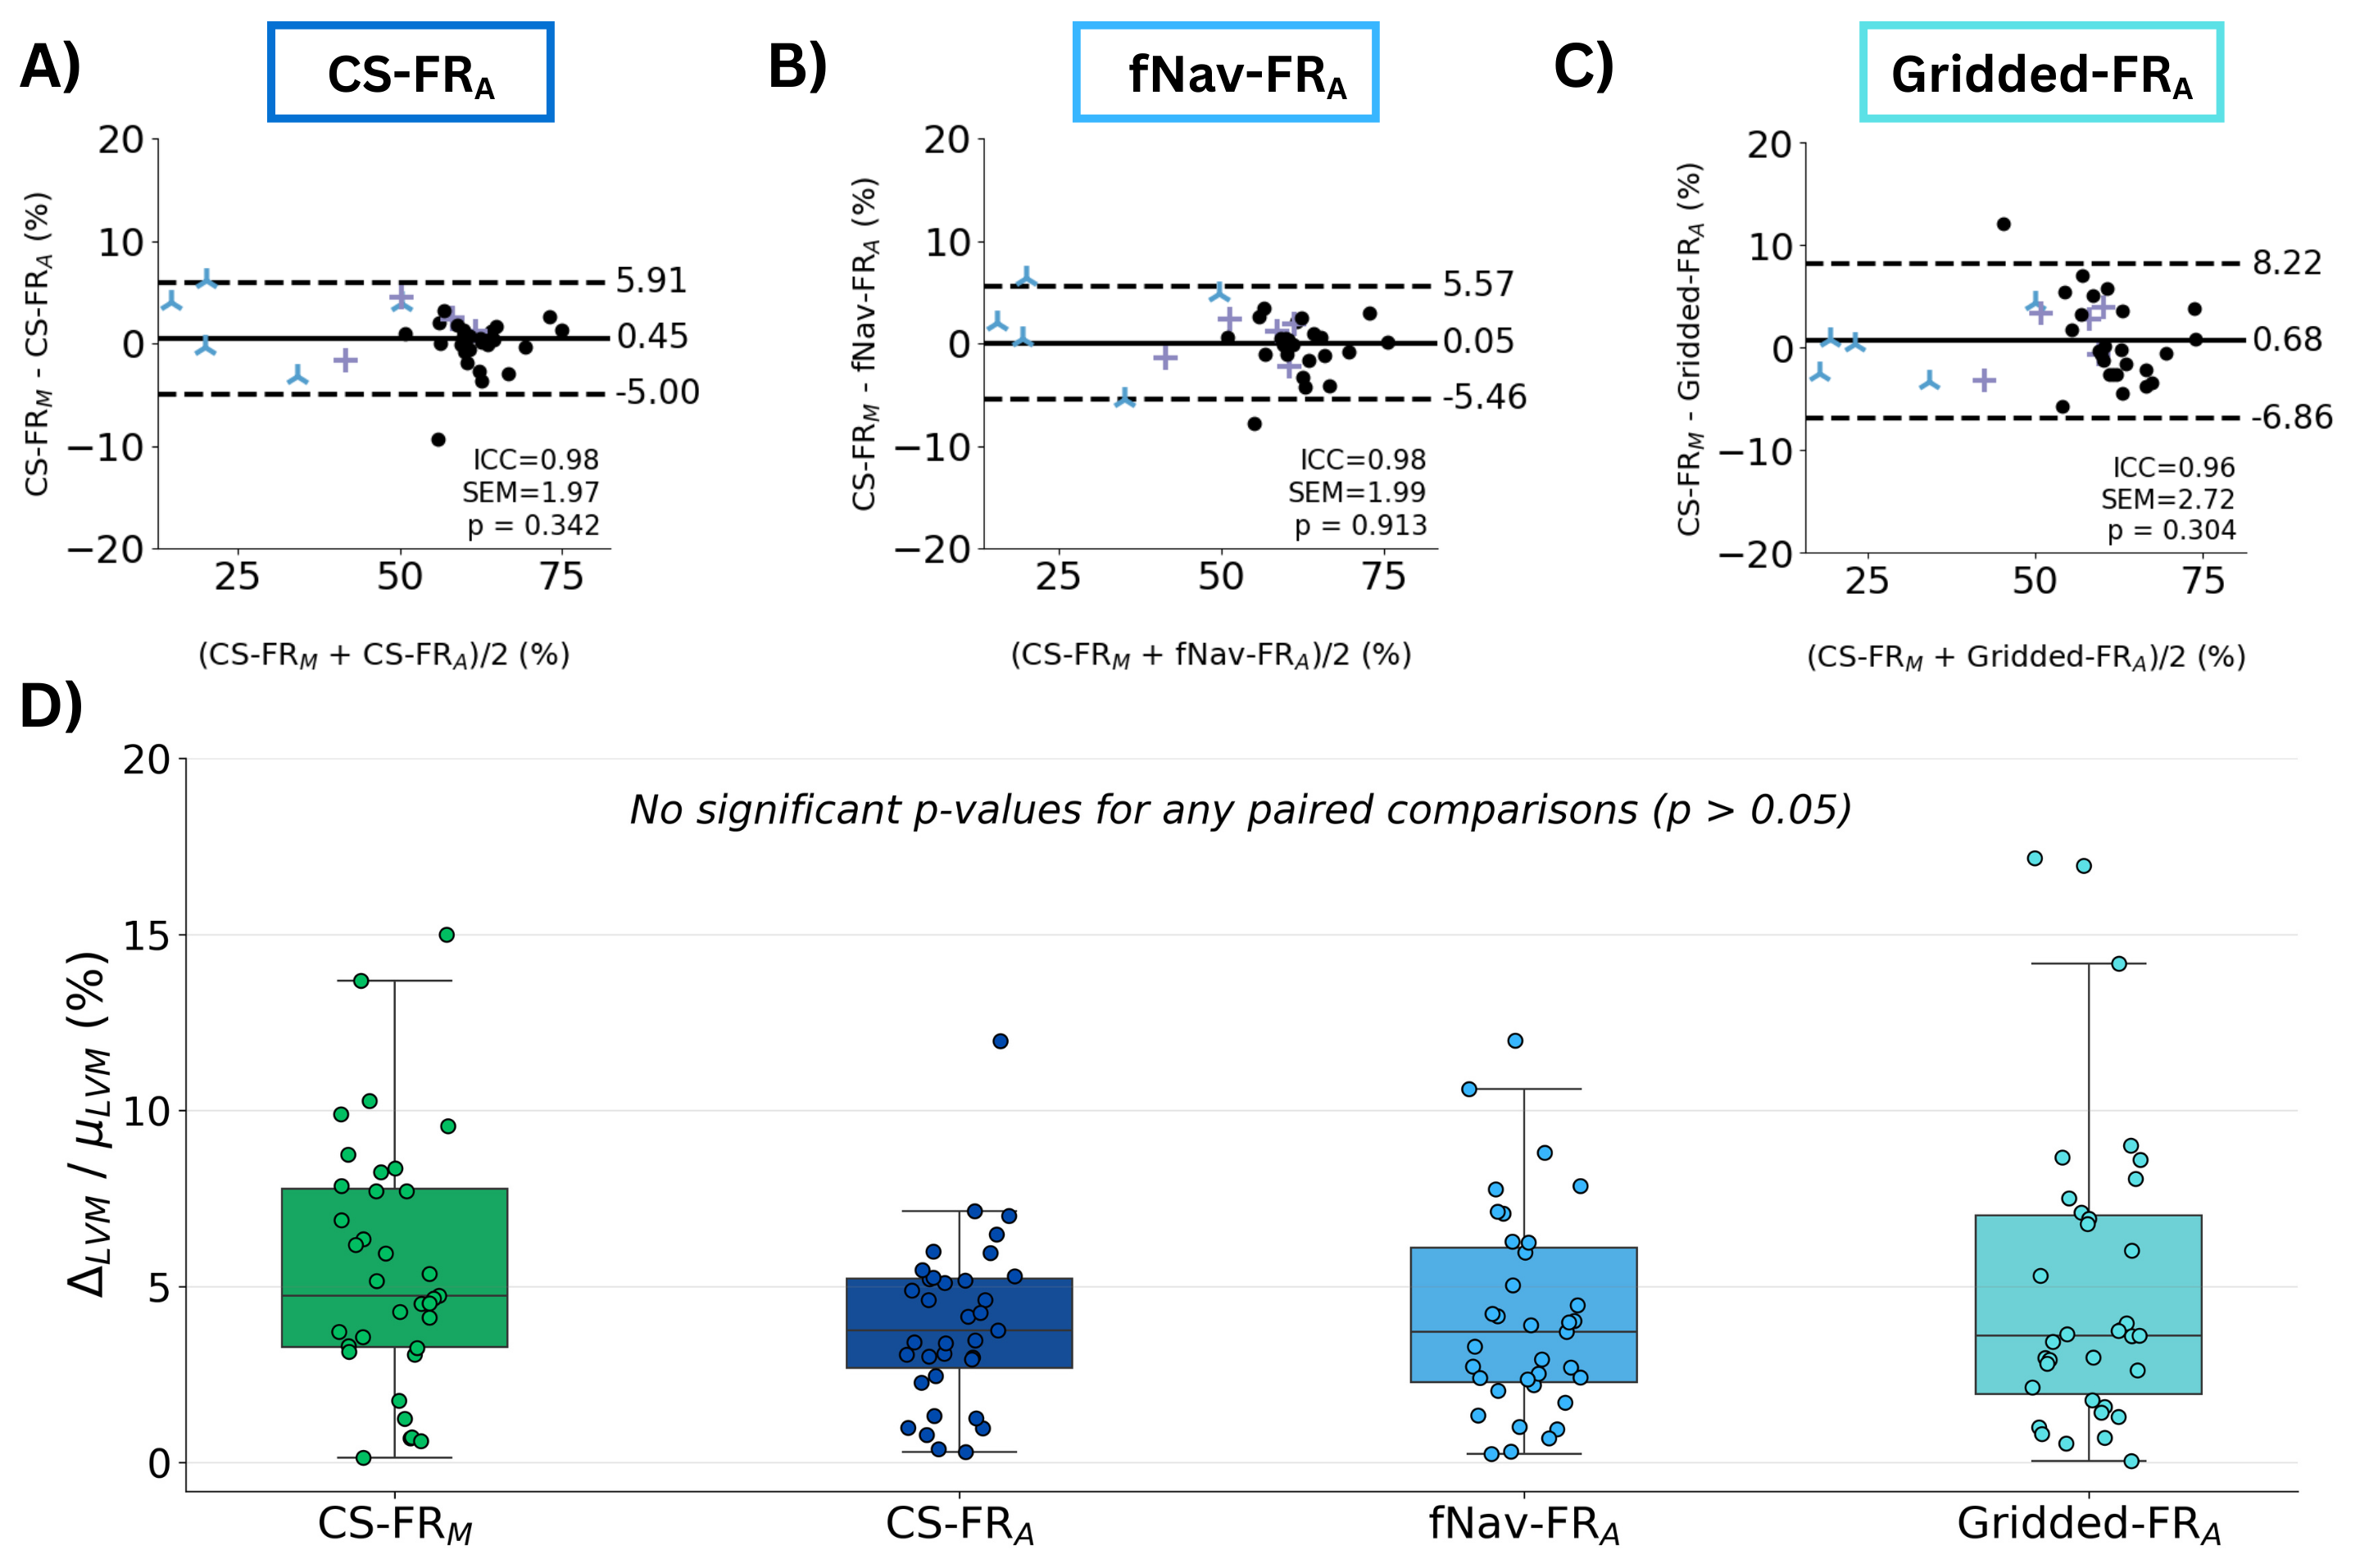

Results: All three automatic segmentations closely matched ground-truth (Fig. 1) with strong geometric accuracy (Table 1). They also demonstrated strong ejection fraction agreement, with negligible bias ( < 1 mL), narrow limits of agreement, and high ICC ( >0.96) (Fig. 2A–C). Myocardial volume was conserved across cardiac phases in all automatic segmentations and did not differ significantly from the ground-truth segmentation (Fig. 2D).

Figure 2: Bland-Altman analysis of left-ventricular ejection fraction comparing semi-manual segmentation on compressed-sensing images (CS-FRM) with the DL-based automatic segmentations trained and applied to A) compressed-sensing images (CS-FRA), B) respiratory motion corrected images (fNav-FRA) and C) gridded images (Gridded-FRA). D) Systolic–diastolic left ventricular myocardial (LVM) volume mismatch computed for each segmentation as the difference between the end-diastole and end-systole volumes (∆_LVM) divided by the mean volume (μ_LVM).

Figure 2: Bland-Altman analysis of left-ventricular ejection fraction comparing semi-manual segmentation on compressed-sensing images (CS-FRM) with the DL-based automatic segmentations trained and applied to A) compressed-sensing images (CS-FRA), B) respiratory motion corrected images (fNav-FRA) and C) gridded images (Gridded-FRA). D) Systolic–diastolic left ventricular myocardial (LVM) volume mismatch computed for each segmentation as the difference between the end-diastole and end-systole volumes (∆_LVM) divided by the mean volume (μ_LVM).